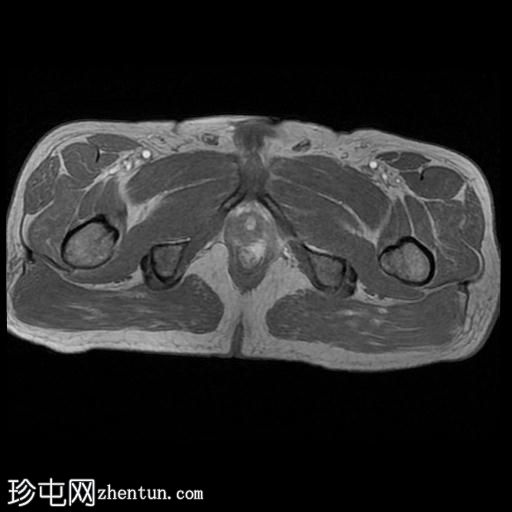

MRI

轴向位

T2

轴向位T2

一条68毫米厚的强化通道始于左侧肛周区域,向上穿过肛门内外括约肌,在2点钟方向开口于肛管。

无脓肿形成。

MRI成像特征与所述左侧经括约肌肛周瘘相符。